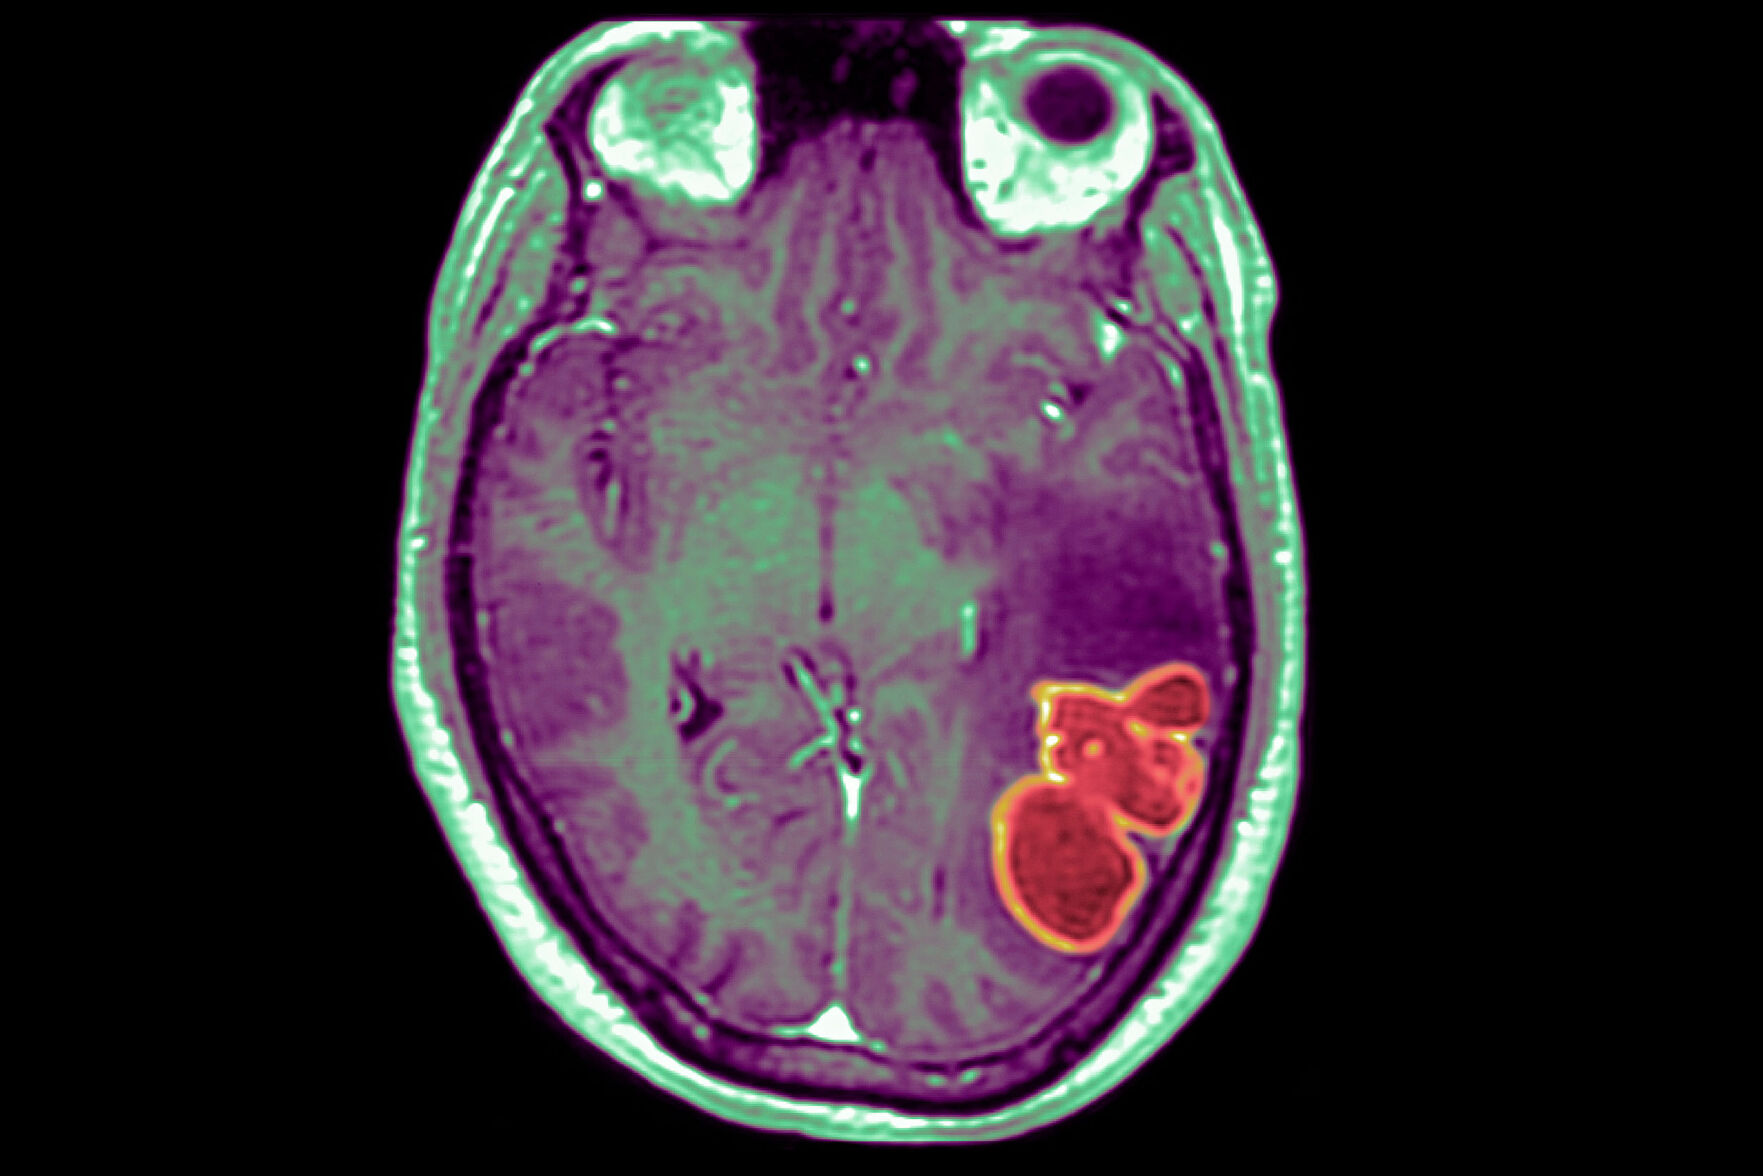

The CDC is investigating a cluster of rare and serious brain abscesses in kids in and around Las Vegas.

Disease detectives with the US Centers for Disease Control and Prevention are investigating …